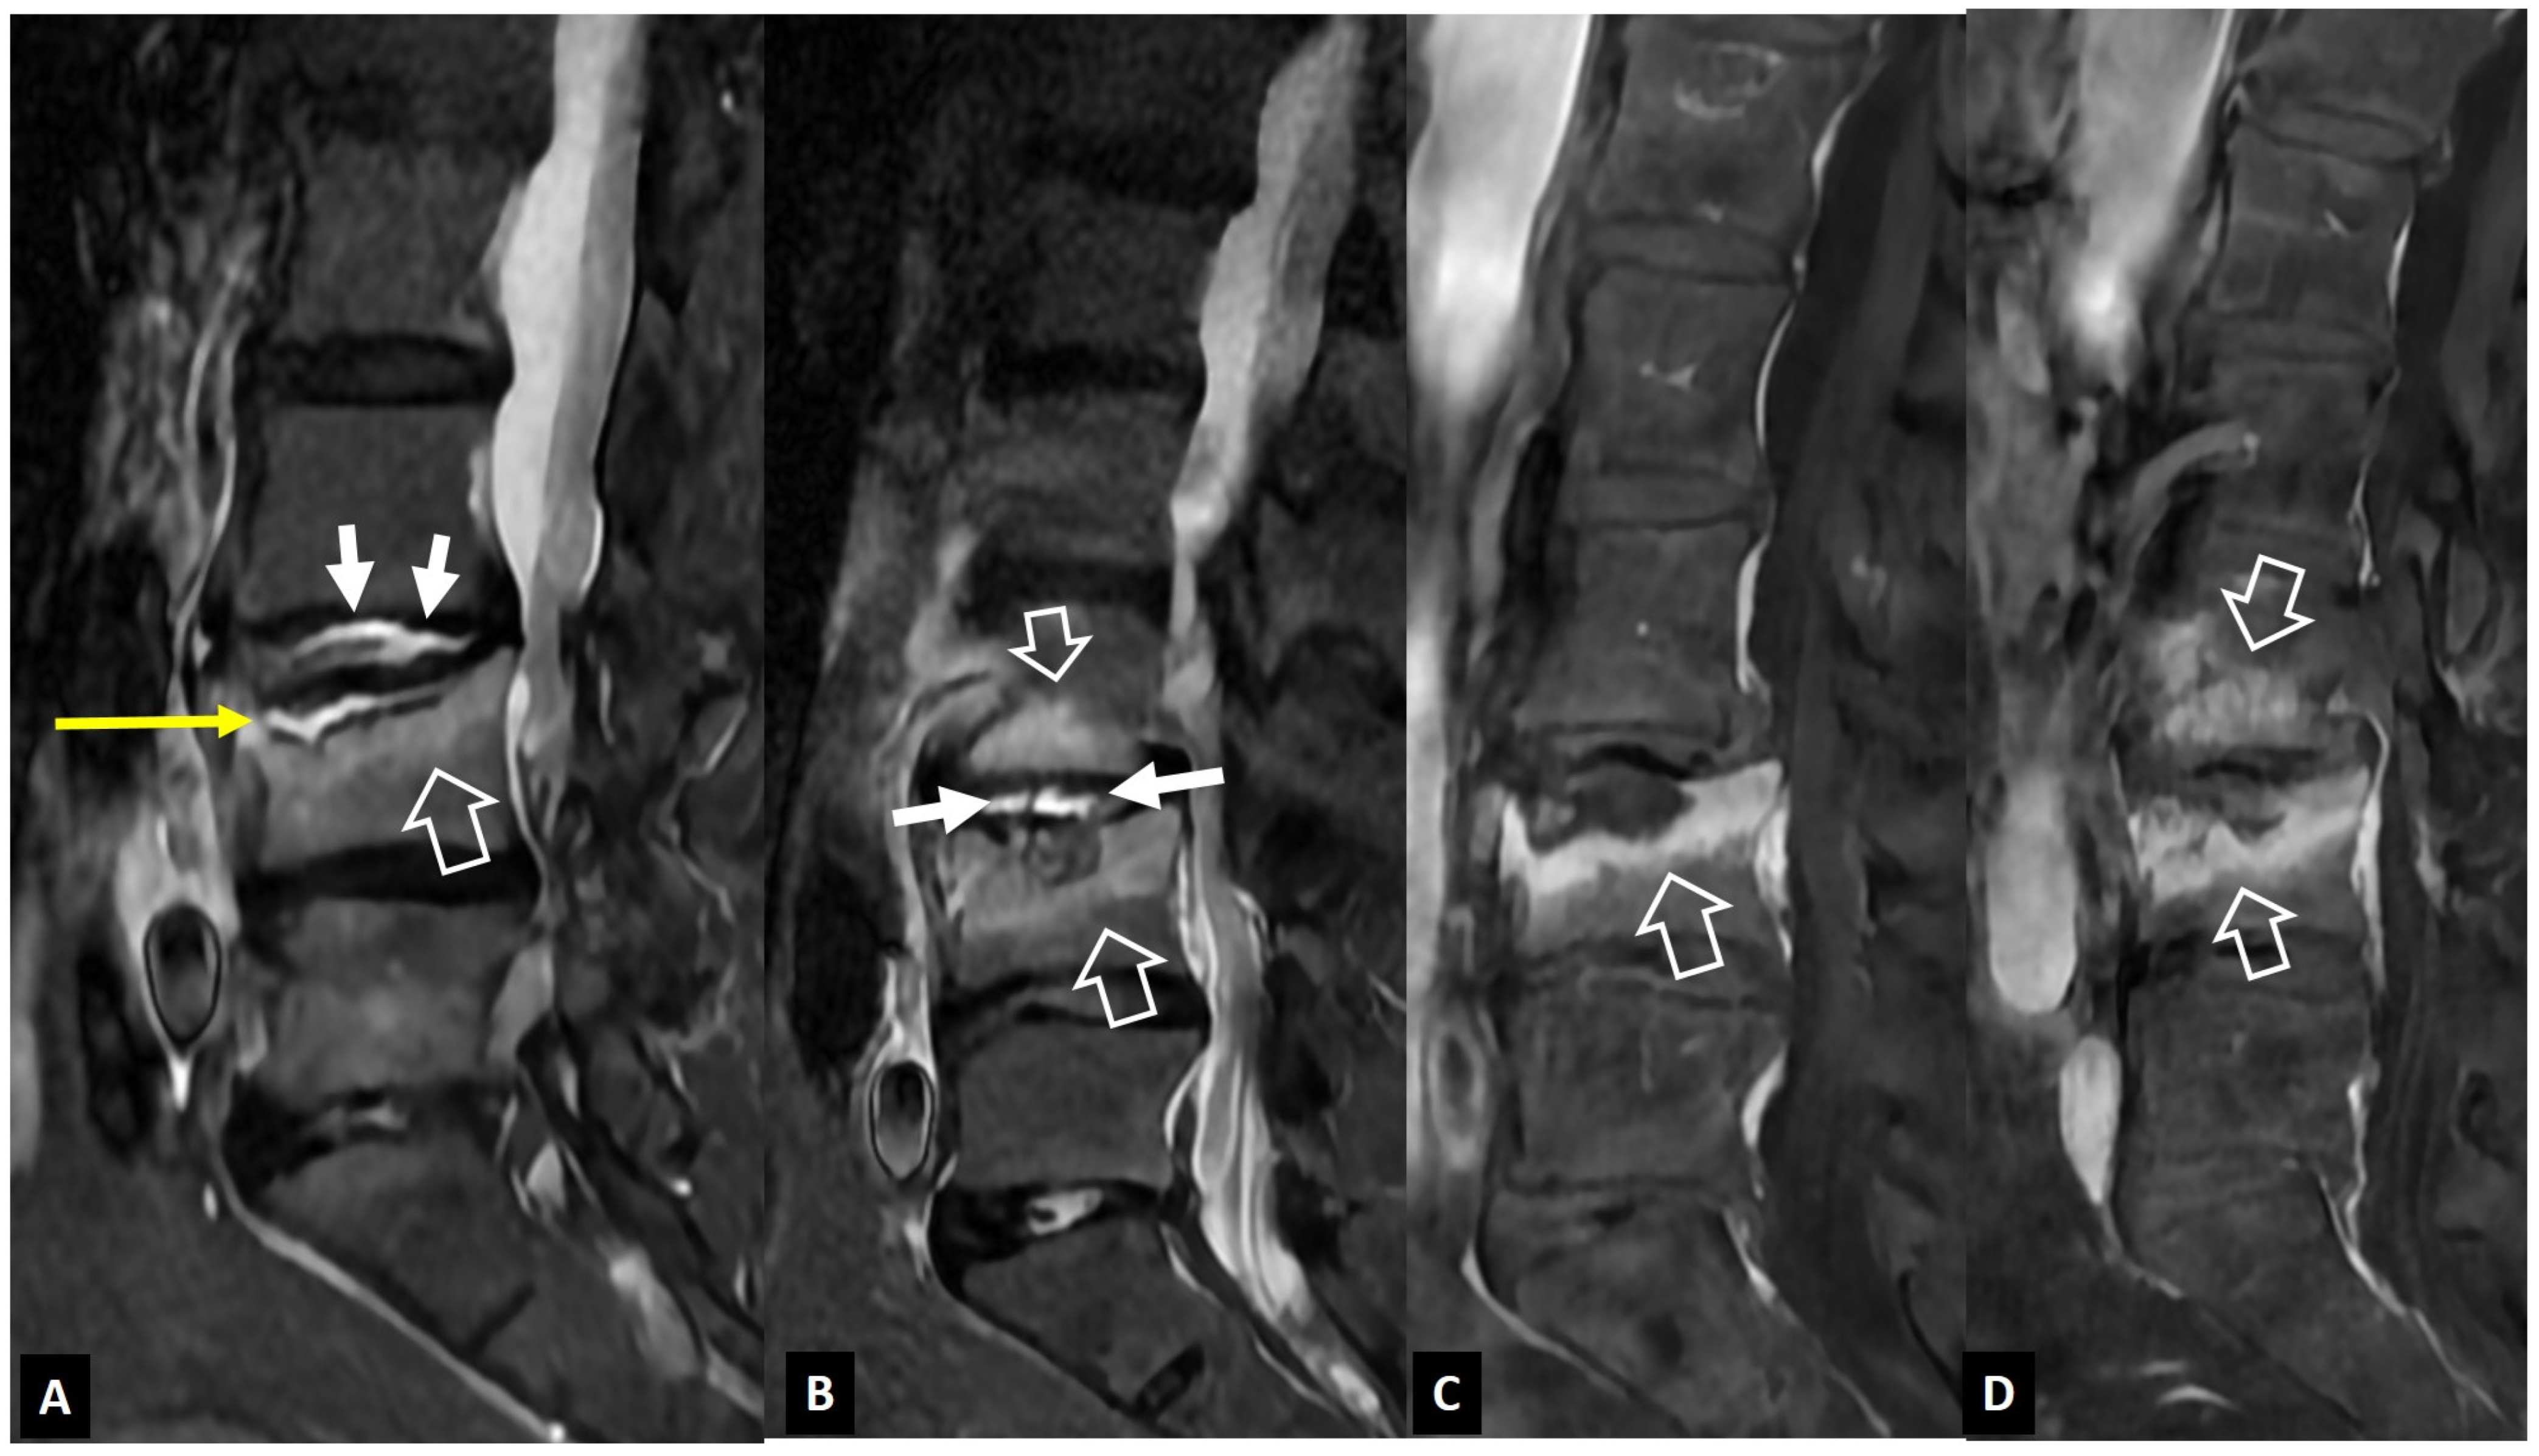

2.1.4. Destructive Spondyloarthropathy

- Kim, S.-K.; Shin, K.; Song, Y.; Lee, S.; Kim, T.-H. Andersson lesions of whole spine magnetic resonance imaging compared with plain radiography in ankylosing spondylitis. Rheumatol. Int. 2016, 36, 1663–1670. [Google Scholar] [CrossRef] [PubMed]

- Bennett, A.N.; Rehman, A.; Hensor, E.M.A.; Marzo-Ortega, H.; Emery, P.; McGonagle, D. Evaluation of the diagnostic utility of spinal magnetic resonance imaging in axial spondylarthritis. Arthritis Rheum. 2009, 60, 1331–1341. [Google Scholar] [CrossRef] [PubMed]

- Kabasakal, Y.; Garrett, S.L.; Calin, A. The epidemiology of spondylodiscitis in ankylosing spondylitis—A controlled study. Br. J. Rheumatol. 1996, 35, 660–663. [Google Scholar] [CrossRef]

- Madsen, K.B.; Jurik, A.G. MRI grading method for active and chronic spinal changes in spondyloarthritis. Clin. Radiol. 2010, 65, 6–14. [Google Scholar] [CrossRef]

- Park, Y.-S.; Kim, J.-H.; Ryu, J.-A.; Kim, T.-H. The Andersson lesion in ankylosing spondylitis: Distinguishing between the inflammatory and traumatic subtypes. J. Bone Jt. Surg. Br. 2011, 93, 961–966. [Google Scholar] [CrossRef]

- Sieper, J.; Rudwaleit, M.; Baraliakos, X.; Brandt, J.; Braun, J.; Burgos-Vargas, R.; Dougados, M.; Hermann, K.G.; Landewé, R.; Maksymowych, W. The Assessment of SpondyloArthritis International Society (ASAS) Handbook: A guide to assess spondyloarthritis. Ann. Rheum. Dis. 2009, 68, ii1–ii44. [Google Scholar] [CrossRef]